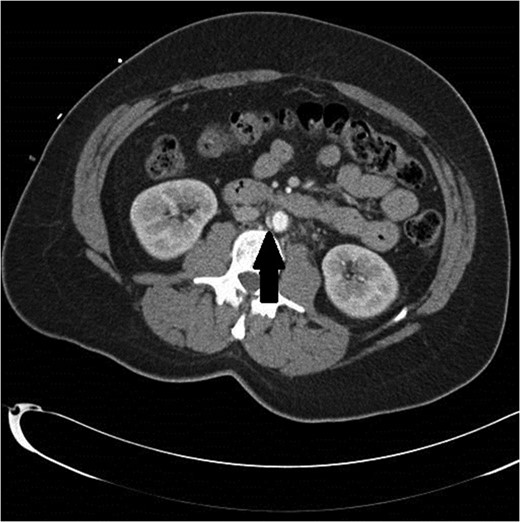

A follow-up CT scan was obtained 3 months later. At the location of the previous aortic abnormality, there was a 3 × 1 cm pseudoaneurysm that had formed and could now be clearly seen (Figs 2 and 3). The patient was asymptomatic.

Black arrow pointing to pseudoaneurysm with enhancing flow outside of the aortic lumen.